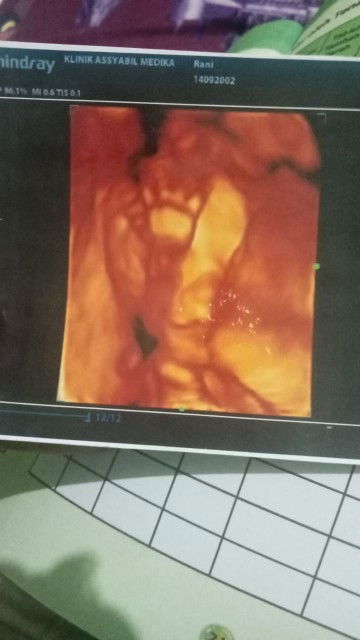

Bun ini foto wktu USG 4d pas hamil 5bln dr nya blg gada kelainan semua normal lengkap baik baik aja tpi knpa ya kmrn USG 2d buat cek posisi bayi ko diblg ini kya ada kelainan di bibirnya smpe di cek 4kli bnr bun kya ada celah gtu pdhl selalu rutin minum vitamin dri bidan trs minum susu hamil jga, gada keturunan sumbing jga dikeluarga aku maupun suami. Anak pertama jga normal sehat lengkap, apa msh ada kemungkinan ya bun bayinya normal gada kelainan nnti pas lahir krna bidan pun msh bingung krna kan USG 2d jdi samar tpi tkutnya benar#seriusnanya #bantusharing